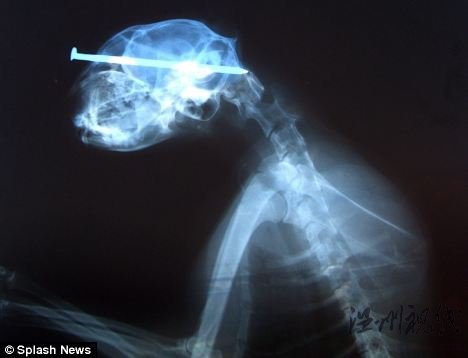

美国小猫头部被插进长钉仍奇迹存活(组图)X光片显示钉子深深地插进小猫的脑袋里。

这只小猫的头部不知被谁插进了一根钉子,然而它走路状况良好,一点也看不出遭受如此厄运。医生将钉子拔出后发现,这个钉子足有3英寸(约7.6厘米)长。当地动物管理中心的辛迪·瑞特说:“我从没见过如此坚强的猫,这样还能活下来,真是令人不可思议。”(海澜)